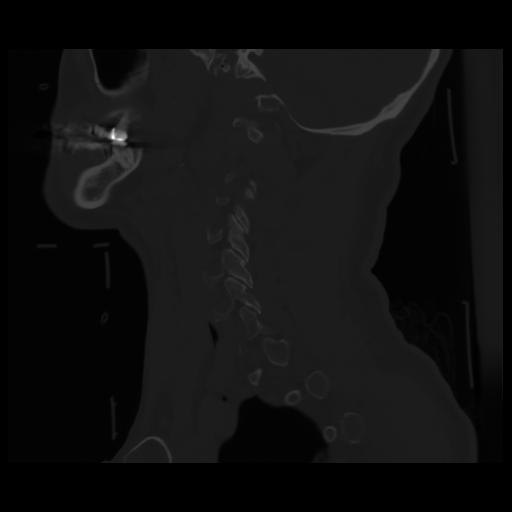

14 P.BLANDAS,,Sagittal,2.000,P.BLANDAS,Sagittal,